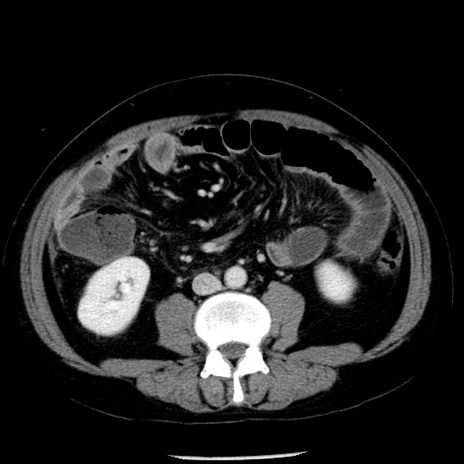

症例29(横断像)

【症例】40歳代男性

【現病歴】2日前から胃痛あり。徐々に周期的な激痛に変化した。本日になっても激痛があるため受診。

【身体所見】意識清明、BT 38-39℃台あり、腹部:膨満、やや硬、右下腹部に圧痛あり。

【データ】WBC 8500、CRP 23.26